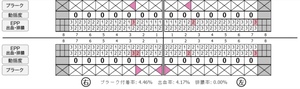

歯周病検査(治療前)

歯周病検査(治療後)

| 担当者所見 | 初診時は、写真を見て分かるように、歯ぐきが赤く腫れていました。 また、歯周病の検査では、全体的に歯と歯の間の部分の歯周ポケットが4ミリあり、全体の約81%から出血が認められました。 出血量も多く、歯ぐきに触れた瞬間に出血しました。 レントゲンで骨のレベルがしっかりとあることが確認できました。 そのため、ご自身で正しい歯磨きを継続することで改善すると考えました。 歯周基本治療を経て、再度検査した結果、歯周ポケットはほぼ3ミリ以下に改善しました。左下7番の残存した歯周ポケットは、隣の親知らずを抜いたため経過観察します。 出血率は約4%まで改善し、出血量も点状で少なくなりました。 今後は右上2番、右下3番の歯ぐきの発赤の改善と、出血率0%を目指して、定期検診でメンテナンスしていきます。 |